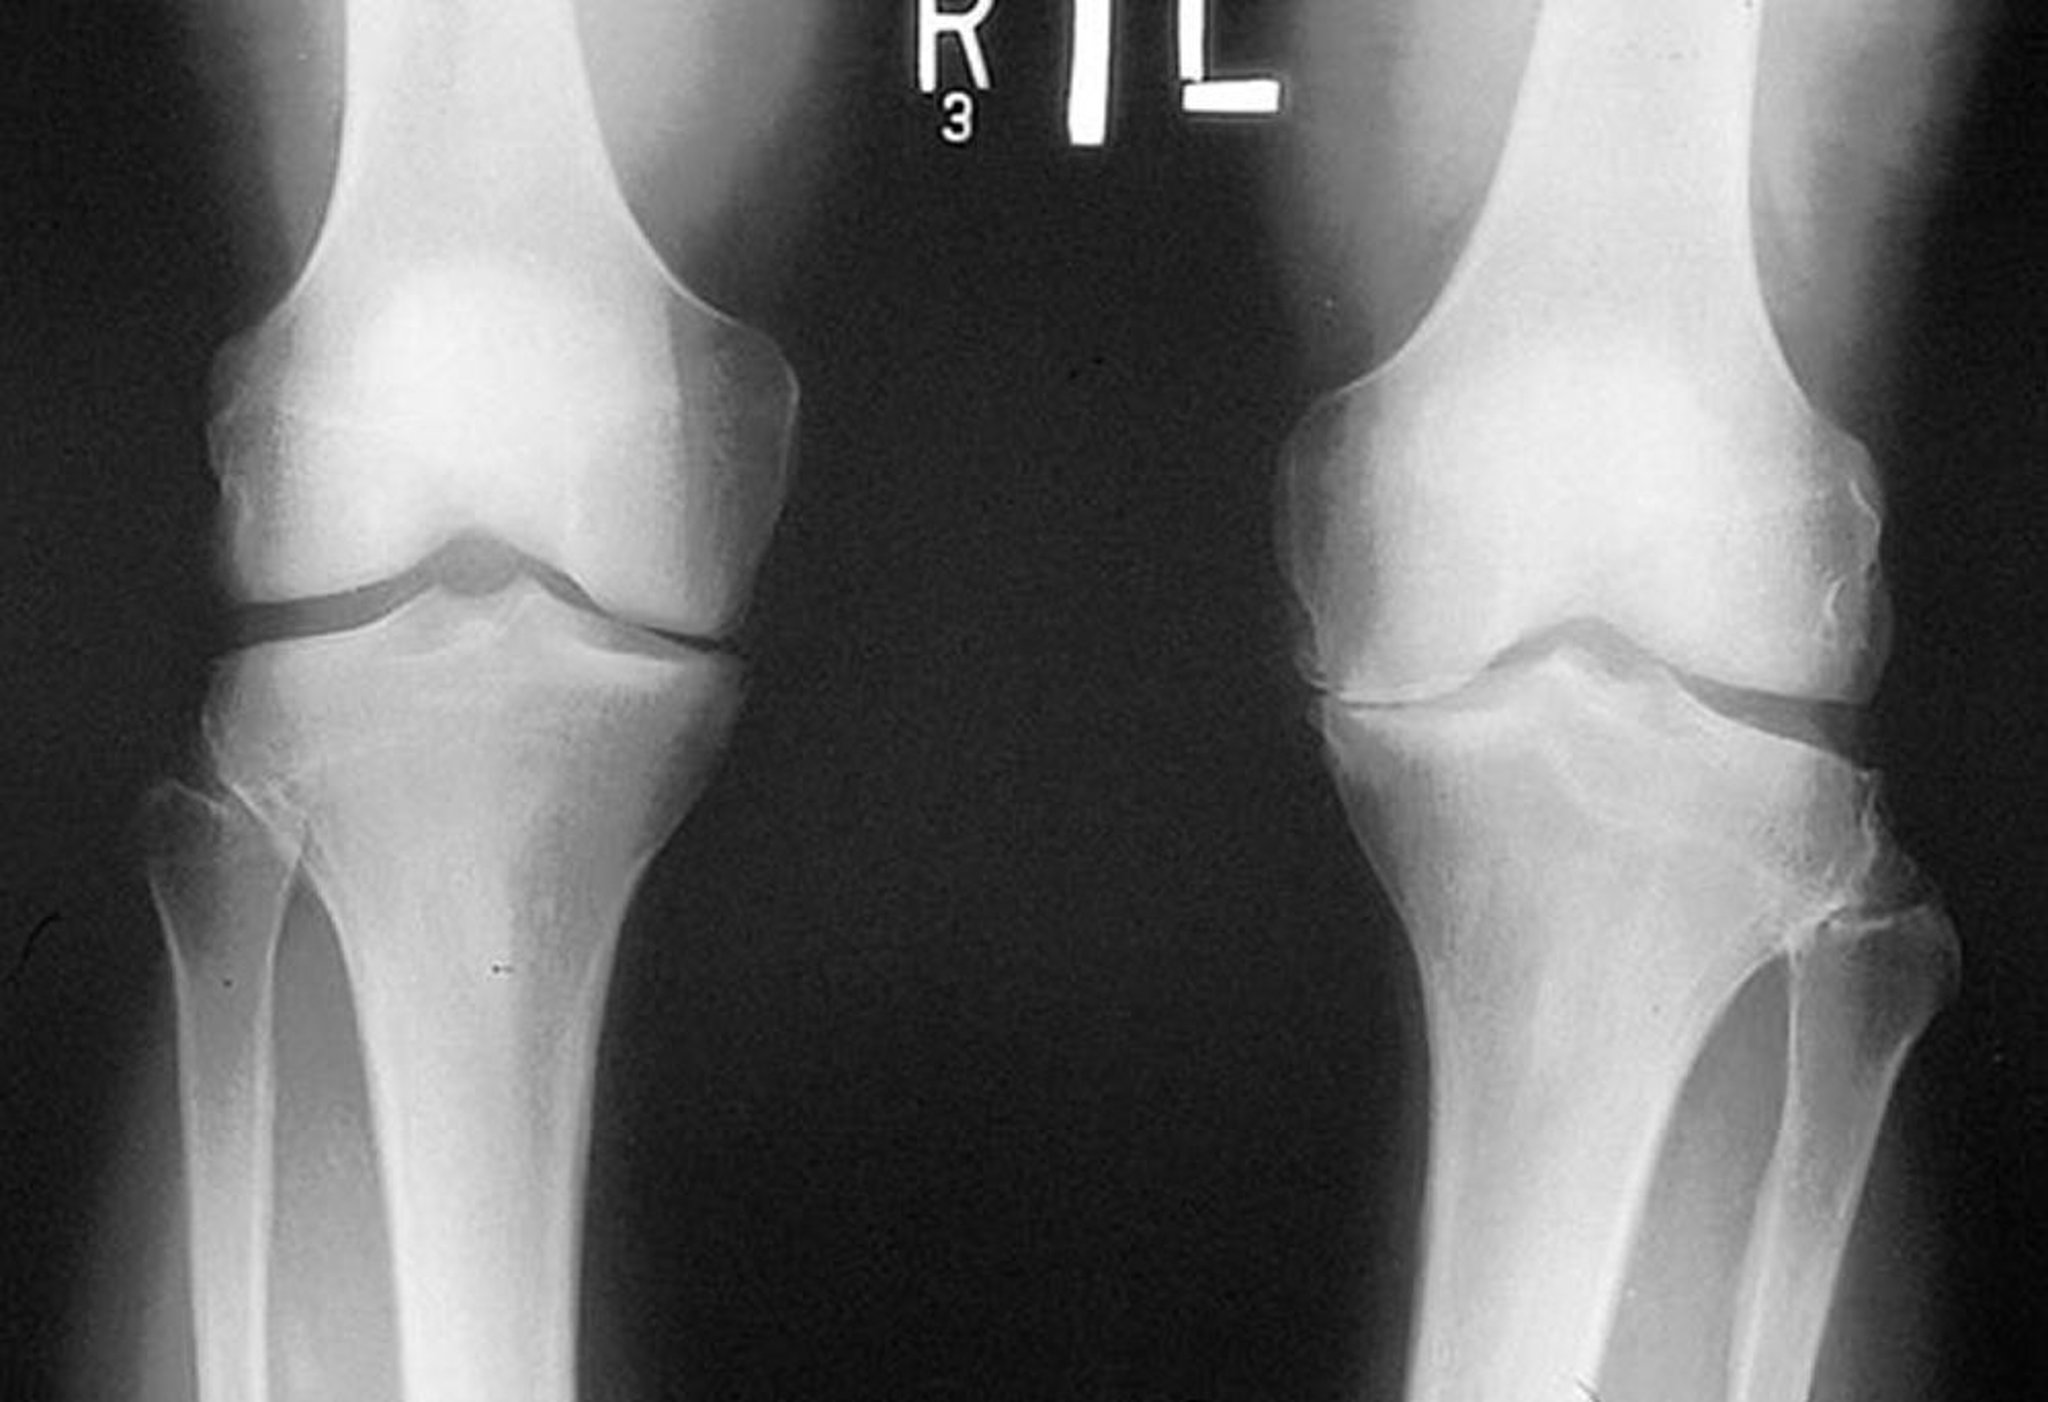

Radiografie del ginocchio nell'artrosi

Questa radiografia, ottenuta mentre il paziente è in piedi, mostra che lo spazio articolare tibiofemorale nel compartimento mediale di entrambe le ginocchia è stretto, in particolare a sinistra. Gli osteofiti marginali sono visibili. C'è attrizione del piatto tibiale mediale sinistro.

By permission of the publisher. From Myers S: Atlas of Rheumatology. Edited by G Hunder. Philadelphia, Current Medicine, 2005.